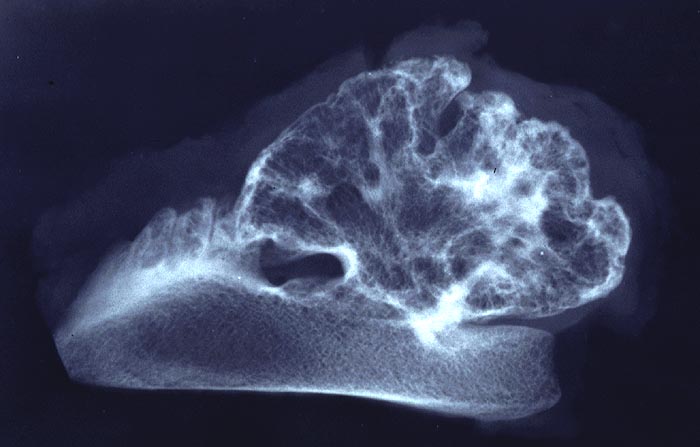

Basel 1MA/ Osteochondrom

Osteochondrom

Im konventionellen Röntgenbild lassen sich gestielte und breitbasige Osteochondrome unterscheiden, wobei letztgenannte Formen immer vom Gelenk weggerichtet sind. Ein wichtiges Charakteristikum ist, dass die Spongiosa des Osteochondroms mit der Spongiosa des ortsständigen Knochens in Verbindung steht und die Läsion nicht einfach nur der Kompakta aufsitzt. Die Knorpelkappe ist im konventionellen Röntgenbild (> 5033) nur angedeutet erkennbar, kann aber im CT, MRI oder im Ultraschall dargestellt und ausgemessen werden. In der Mehrzahl der sporadischen aber v.a. der hereditären Osteochondrome lassen sich biallelische Inaktivierungen des EXT1 oder EXT2 Gens nachweisen, was die neoplastische Genese der Läsionen unterstreicht.

• Kappenförmiges hyalines Knorpelgewebe ohne Zellatypien sitzt auf einem knöchernen Stiel. Die Knorpelkappe ist 2mm dick.

• Übergang des Knorpels in enchondrale Ossifikationszone wie in einer Epiphysenfuge: Knochen wird abgelagert entlang von linearen Knorpelsäulen.